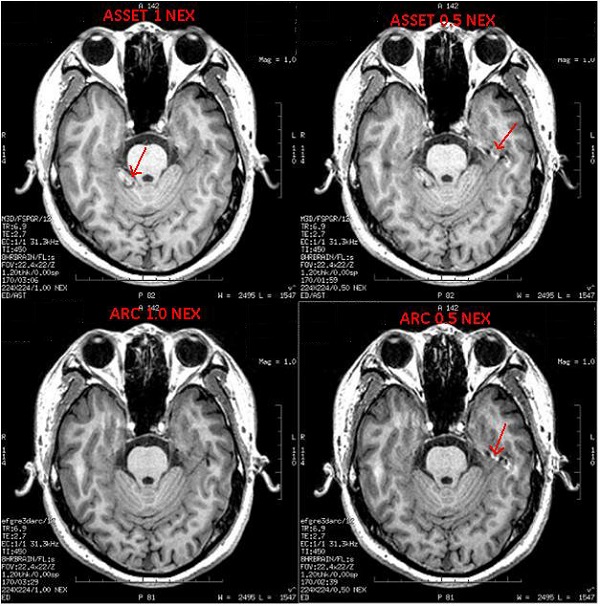

Figure 2. ASSET 1 NEX images demonstrates aliased ear artifact in the center of the image while ARC image projects aliased anatomy to the edges of the FOV. Both 1/2 NEX ARC and ASSET images are sensitive to in-flow artifacts on axial images.